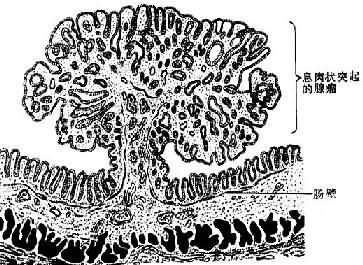

1.乳头状瘤(papilloma)由覆盖上皮发生,向表面呈外生性生长,形成许多手指样或乳头状突起,并可呈菜花状或绒毛状外观。肿瘤的根部常较狭窄成蒂与正常组织相连。镜下,每一乳头由具有血管的分支状结缔组织间质构成其轴心,其表面覆盖的增生上皮因起源部位不同而异,可为鳞状上皮(图7-9)、柱状上皮或移行上皮。在外耳道、阻茎及膀胱和结肠的乳头状瘤较易发生恶变而形成乳头状癌,值得注意。

图7-9 皮肤乳头状瘤

2.腺瘤(adenoma)是由腺上皮发生的良性肿瘤,多见于甲状腺、卵巢、乳腺、涎腺和肠等处。粘膜腺的腺瘤多呈息肉状(图7-10),腺器官内的腺瘤则多呈结节状,且常有包膜,与周围正常组织分界清楚。腺瘤的腺体与其起源腺体不仅在结构上十分相似,而且常具有一定的分泌功能。不同这外仅在于腺瘤的腺体大小、形态较不规则,排列也比较密集。发生于有小叶和导管结构的器官的腺瘤,其小叶结构往往缺如或不明显,亦无导管形成,故不能将其分泌物排出。

图7-10 肠的息肉状腺瘤模式图

(4)息肉状腺瘤(polypous adenoma) 发生于粘膜,呈息肉状,有蒂与粘膜相连,多见于直肠(图7-10),其中表面呈乳头状或绒毛状者恶变率较高。本瘤亦见于结肠、胃等处,结肠多发性腺瘤性息肉常有家族遗传性,不但癌变率很高,并易早期发生癌变。